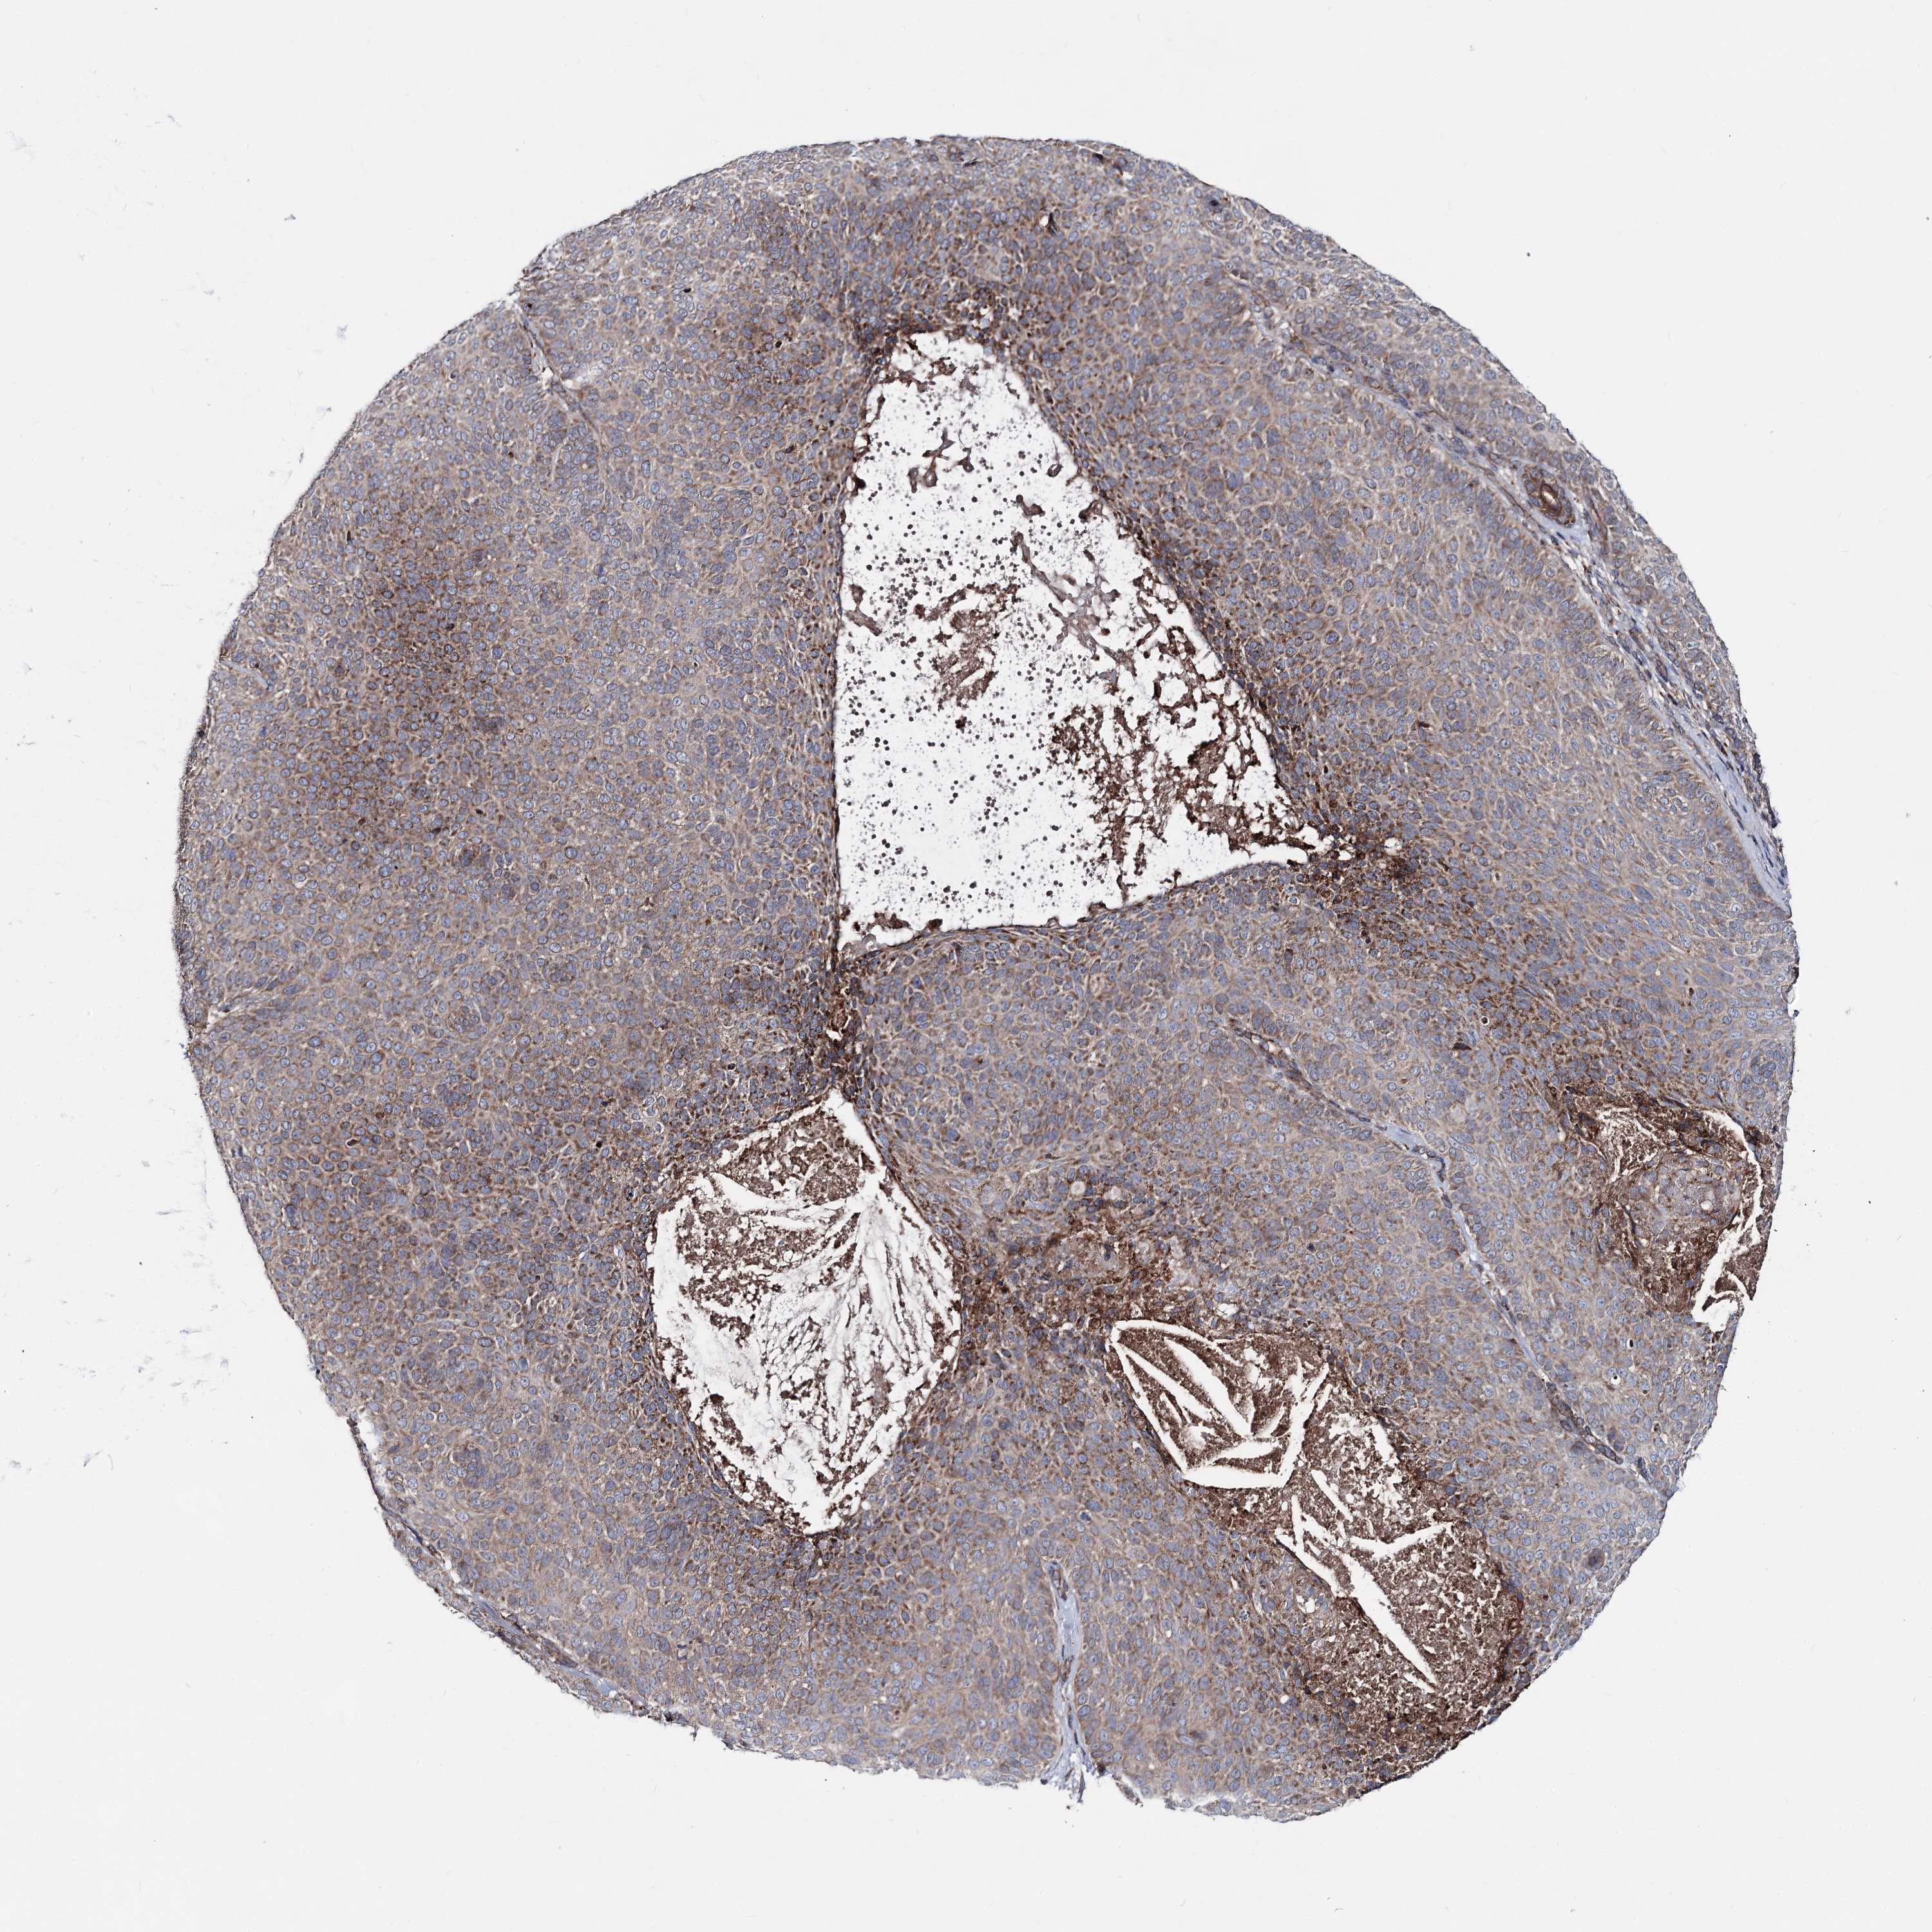

Basal cell and squamous cell cancer

SKIN CANCER - Protein expressioni

A mouse-over function shows sample information and annotation data. Click on an image to view it in a full screen mode. Samples can be filtered based on level of antibody staining by selecting one or several of the following categories: high, medium, low and not detected. The assay and annotation is described here.

Each image is clickable and will lead to virtual microscopy that enables deeper exploration of all samples and also displays staining intensity scores, fraction scores and subcellular localization as well as patient and tissue information for each sample.

Antibody HPA038694

Antibody HPA038695

Squamous cell carcinoma, NOS